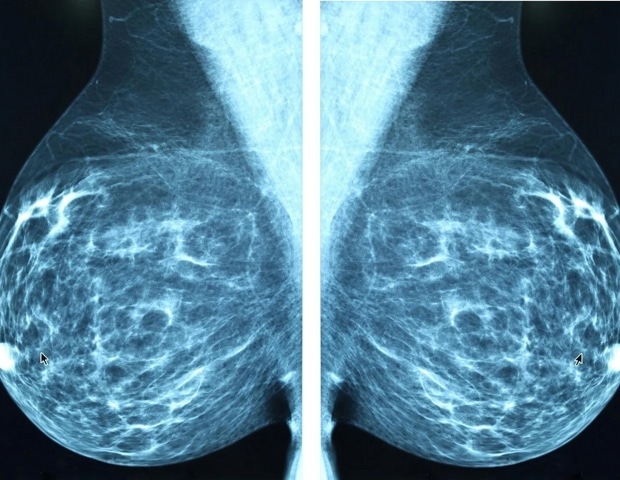

מחקר של נתונים משבעה מרפאות חוץ באזור ניו יורק מצא כי 20-24% מכלל מקרי סרטן השד שאובחנו במהלך תקופה של